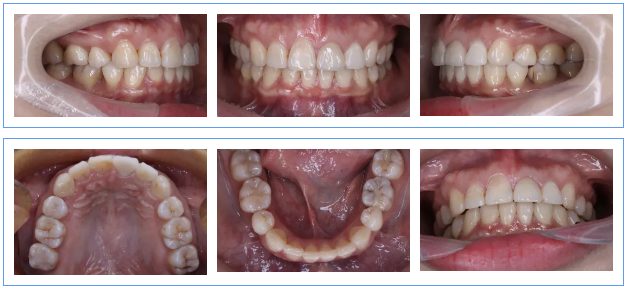

五、治疗结束

1.微笑美学改善,患者治疗前前牙残根、龋坏、牙龈炎,严重影响微笑美观。通过系统化治疗,恢复前牙的形态、获得牙龈健康、牙齿良好的排列。使得笑容美观得到提升。

2.21牵引修复,21残根长度12mm,牙槽骨内根长11mm,完善根管治疗术后,通过矫正合向牵引2mm,骨内剩余长度9mm,最终完成桩冠修复,冠根比例1:1。21在使用过程中健康稳定。

3.侧貌美观,正畸治疗在关闭多颗(14、24、35、45、17)拔牙间隙过程中,为避免过度内收影响患者面型美观,采取下颌弱支抗、上颌中等支抗设计,最终内收完成上下前牙处于理想位置,收获良好的侧貌美观。

4.后期稳定性。患者患龋风险高,通过问诊检查发现与饮食习惯以及口腔保健意识有直接关系,治疗过程中通过OHI,患者掌握较好的刷牙、牙线使用方法,同时戒除碳酸饮料,1年复查没有新发龋坏,并且通过菌斑染色显示菌斑控制良好。